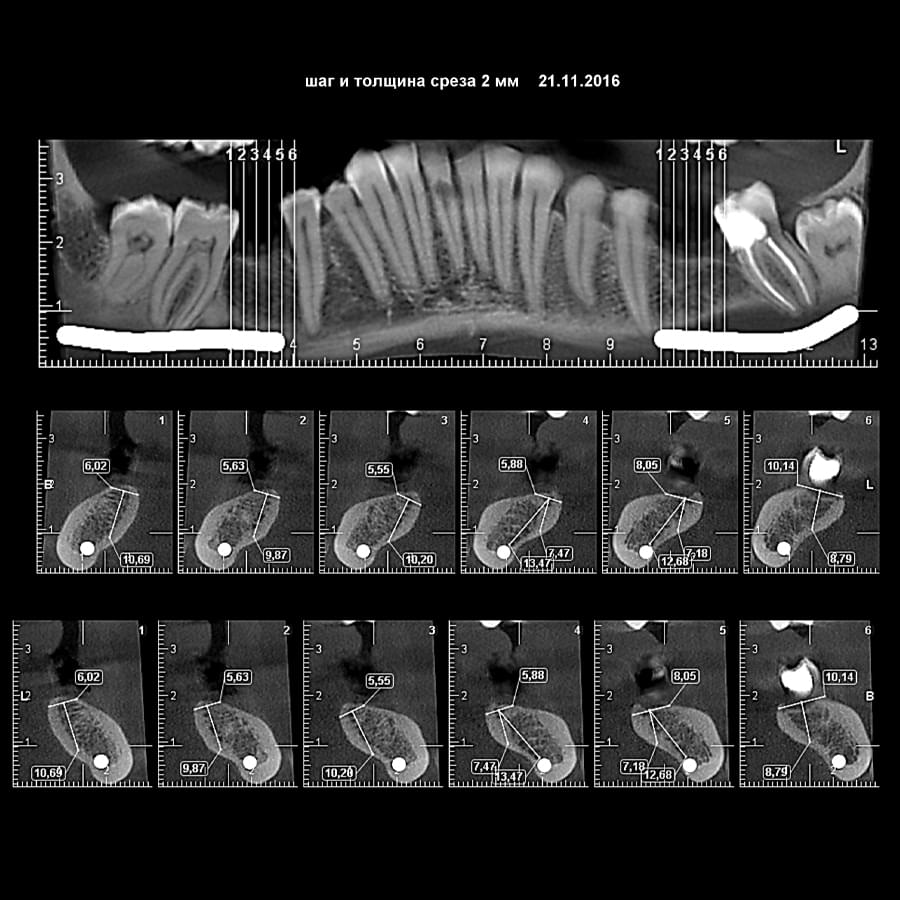

Візуальне порівняння (Кейс одного пацієнта)

Зуб — це не просто монолітний об'єкт, а складна система мікроканалів. На плоскому 2D-знімку вони часто перекривають один одного, створюючи ілюзію простої анатомії.

Непомічений канал — це джерело майбутньої інфекції та причина «загадкового» болю після лікування. Завдяки високій роздільній здатності обладнання MyRay, лікар бачить кожен мікронний канал ще до того, як візьме до рук інструмент.